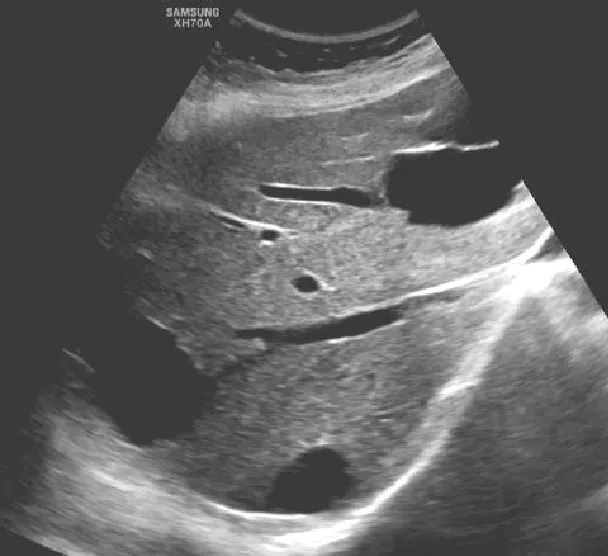

肝脓肿

● 定义:肝脓肿是肝脏的化脓性炎症,可由细菌、真菌或阿米巴原虫等感染引起。病理过程通常包括炎症浸润期、脓肿形成期和脓肿吸收期。

● 超声表现:

1.肝内单个或多个占位性病变。

2.早期呈低回声,边界不清,血流丰富。

3.脓液形成后,呈液性暗区,壁厚薄不均,内壁不平整,内透声差,可见絮状回声,有些可见分层。

4.肝脓肿进一步发展,内透声好,如肝囊肿,但壁厚薄不均。

5.后方结构(后壁)回声增强。